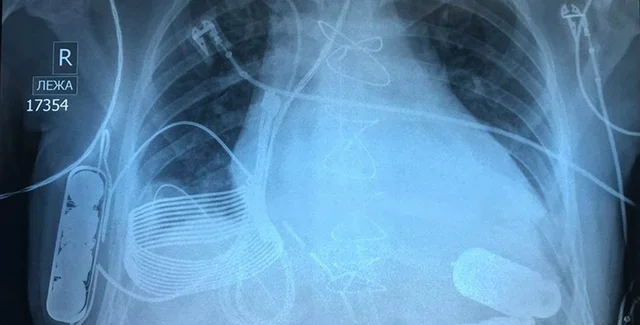

Уникальные устройства спасли бесчисленное количество жизней. Сейчас технология вышла на новый уровень: ученым впервые удалось вживить в грудь 24-летнего мужчины из Казахстана, страдающего от сердечной недостаточности последней стадии, устройство, которое заряжается беспроводным способом.

Операция была проведена в Национальном исследовательском центре кардиохирургии в Астане, говорится в сообщении израильской технологической компании Leviticus Cardio.

Новое устройство не нуждается в проводе питания благодаря системе зарядки, созданной израильской технологической компанией Leviticus Cardio. Система состоит из индуктивной катушки приемника, аккумулятора внутреннего контроллера — все они имплантированы в грудь пациента. От одного заряда устройство может проработать около восьми часов.